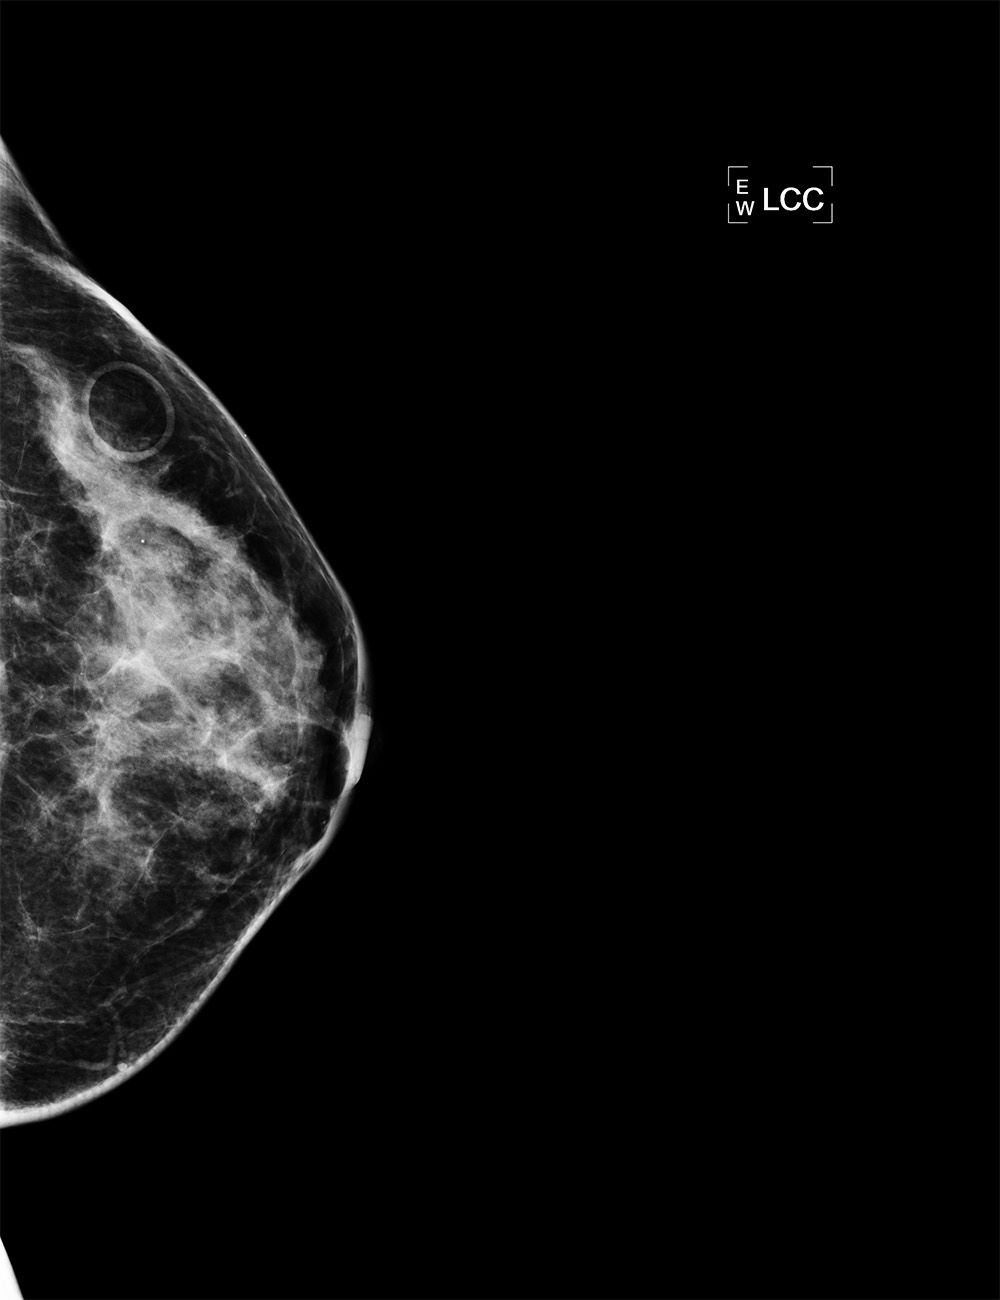

52-year-old asymptomatic female with family history of breast cancer presents for annual mammogram.